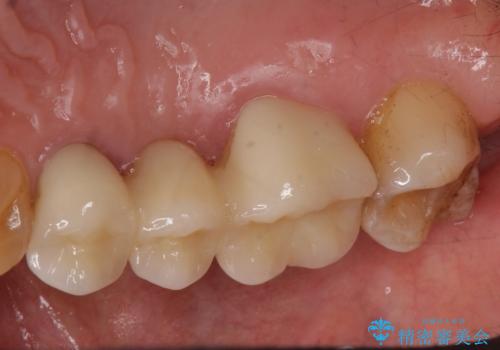

- 他院でブリッジの仮歯を入れたが、外れやすいため転院を希望された患者様です。

支台歯の形が角度が大きくついた形に形成してあり、外れやすい形になっていたため修正してから歯型をとりました。

- 36.3万円(ジルコニアクラウン10万円x3本)費用は治療当時の料金となります

根の治療のやり直しは特に行っていません。